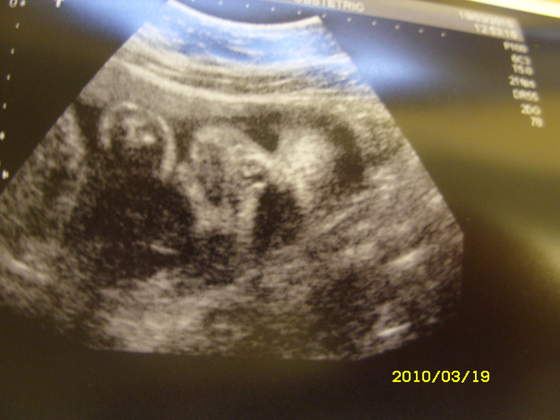

Nasze fasolki na USG

witam pokaże Wam moją córeczkę - jeśli mi się uda :baffled: